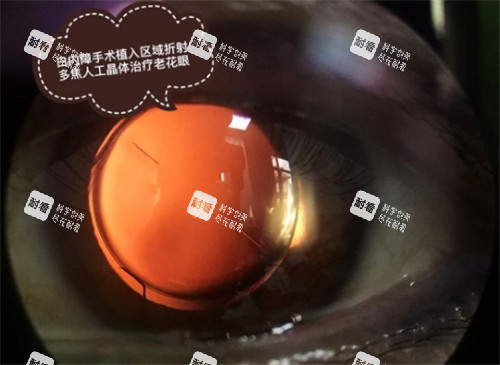

项目通常会包含指定的国产人工晶体和基本手术费、药费、检查费。

若患者选择更高端别的人工晶体,可能需要自付差价。

选择高端晶体: 如果患者希望使用更优质的非球面、多焦点、散光矫正型等进口或高端人工晶体,超出项目提供晶体范围的部分,需要患者自行承担差价。